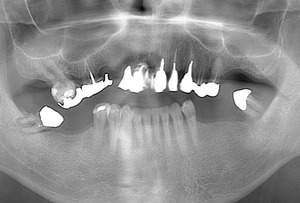

患者様の初診時レントゲン写真

【担当医師所見】

咬合平面の整頓の必要性 有

交叉咬合、オーバージェットの是正

歯周病の治療の必要性

ブラッシング方法の教授

左右上下合わせて4本の抜歯を行った